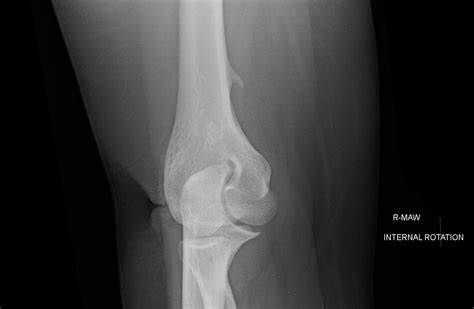

To determine if you have a bone spur elbow, a healthcare professional will typically conduct a physical examination followed by imaging studies. During the physical exam, they will test your range of motion and look for areas of tenderness. Imaging is essential to confirm the diagnosis and assess the extent of the growth.

X-Ray The most common method to visualize bone density and identify bony projections.